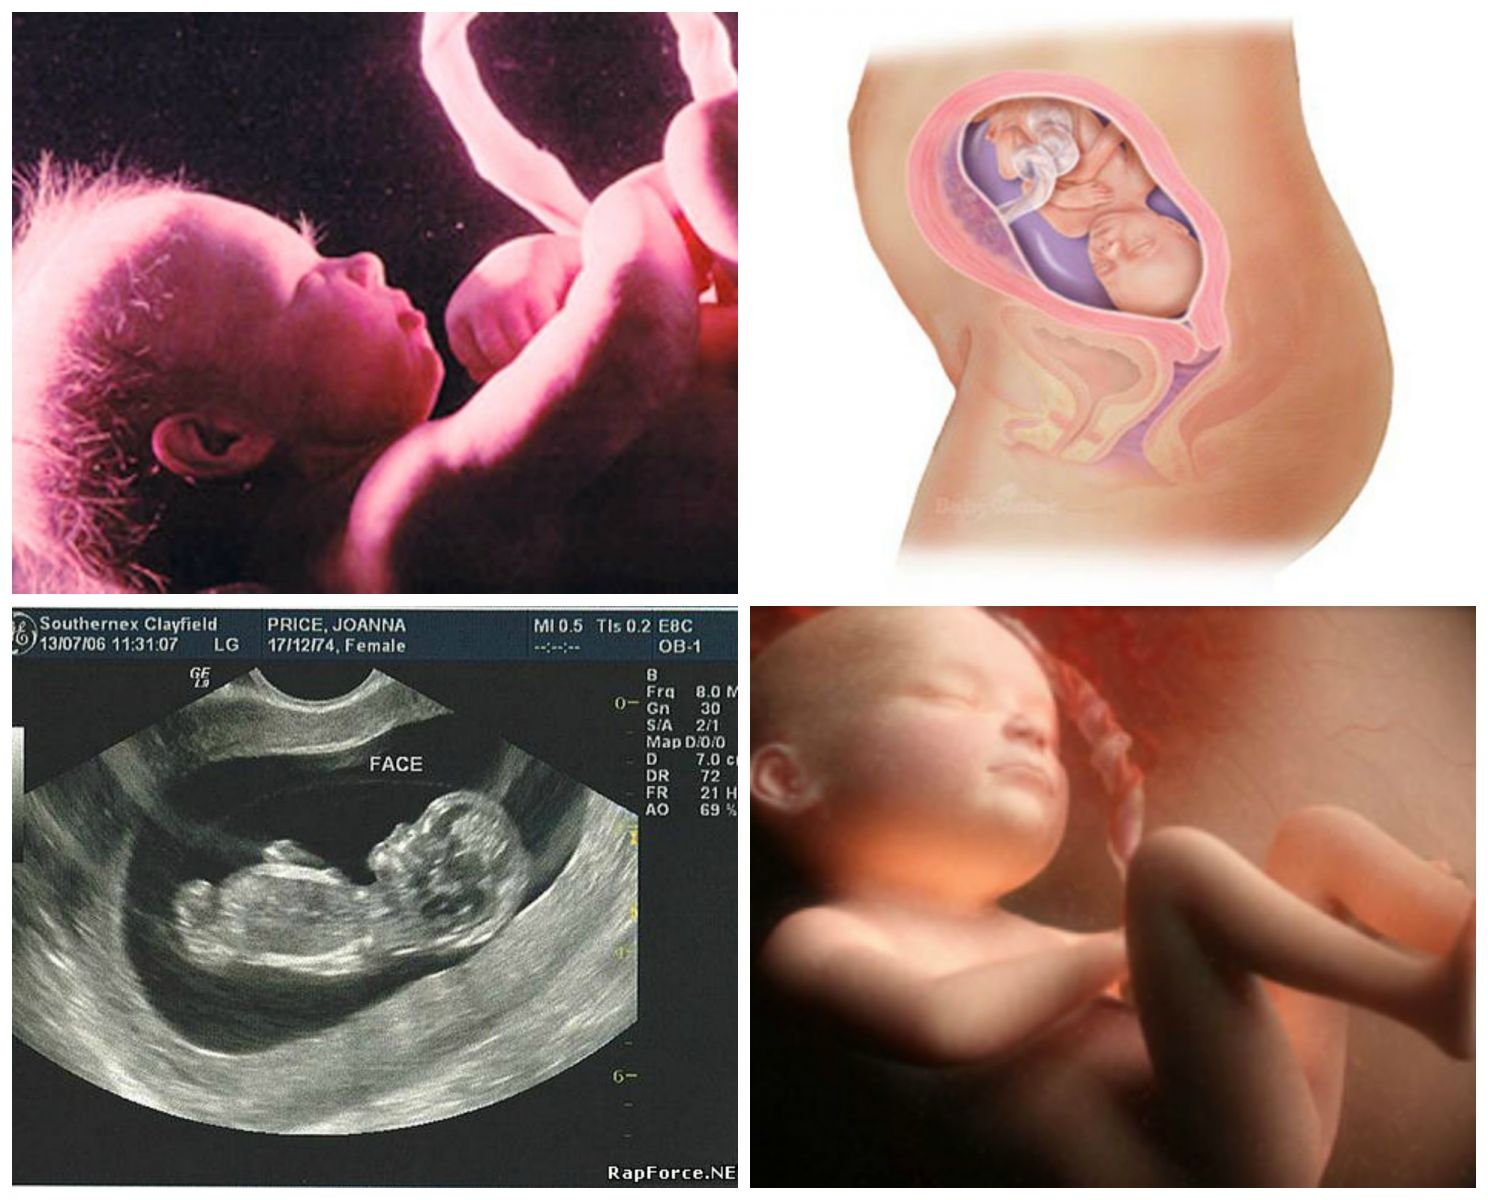

На 27-й неделе беременности происходит множество важных изменений как у малыша, так и у мамы. Врачи отмечают, что к этому времени плод достигает длины около 36 см и весит около 900 граммов. Его органы продолжают развиваться, а легкие готовятся к самостоятельному дыханию. Малыш активно двигается, что свидетельствует о его здоровье и развитии.

Для мамы этот период может быть как радостным, так и непростым. Увеличение живота приводит к физическому дискомфорту, а гормональные изменения могут вызывать перепады настроения. Врачи рекомендуют уделять внимание своему состоянию, правильно питаться и заниматься легкой физической активностью. Также важно следить за регулярными визитами к врачу, чтобы контролировать здоровье как мамы, так и малыша. Визуализация этого периода через фото помогает будущим родителям лучше понять, как растет их ребенок и какие изменения происходят в их жизни.

| Развитие: Легкие активно развиваются, готовясь к дыханию. Мозг продолжает формироваться, появляются новые извилины. Глазки открываются и закрываются, малыш реагирует на свет. | Ощущения: Матка продолжает расти, давит на внутренние органы, вызывая изжогу, одышку, частые позывы к мочеиспусканию. Могут появиться отеки ног и рук. | Малыш: Примерно 36-37 см в длину, весит около 900-1000 грамм. Кожа становится менее прозрачной, под ней накапливается жир. |

| Движения: Малыш активно двигается, пинается, переворачивается. Вы можете чувствовать его икоту. | Изменения в теле: Живот значительно увеличился, центр тяжести сместился, что может вызывать боли в спине. Грудь продолжает увеличиваться, возможно выделение молозива. | Мама: Живот заметно округлился, пупок может выпячиваться. Возможно появление растяжек на животе, бедрах и груди. |

| Слух: Слух хорошо развит, малыш различает голоса родителей, реагирует на музыку и громкие звуки. | Эмоции: Настроение может быть переменчивым из-за гормональных изменений. Возможны тревога и волнение перед родами. | УЗИ: На УЗИ можно увидеть, как малыш сосет пальчик, зевает, открывает и закрывает глазки. |

| Сон: У малыша формируются циклы сна и бодрствования. Он может спать до 16-18 часов в сутки. | Подготовка к родам: Возможно появление тренировочных схваток (Брекстона-Хикса). Важно начать посещать курсы для будущих родителей. | Внутриутробное фото: Малыш выглядит как миниатюрный новорожденный, но с более тонкой кожей и меньшим количеством подкожного жира. |

На 27-й неделе беременности ваш малыш по размеру сопоставим с капустой, достигая почти 37 сантиметров в длину и весит около 1250 граммов. Это почти в два раза больше его веса по сравнению с прошлой неделей! Если вы сделаете ультразвуковое исследование, то сможете увидеть, как он удобно устроился в матке.

Развитие мозговой ткани вашего ребенка продолжается, и его мозговая активность возрастает. На этом этапе малыш уже начинает пробовать ту пищу, которую вы употребляете, через амниотическую жидкость. Он также научился открывать и закрывать глаза. Радужная оболочка его глаз начинает приобретать цвет, который может измениться даже после рождения.

На 27-й неделе беременности ваш ребенок способен слышать ваш голос более четко, и он или она может отличить его от других звуков! Малыш также улавливает ваше сердцебиение, звуки, исходящие из вашего живота, и музыку, звучащую снаружи. Все эти звуки воспринимаются немного приглушенно, не только из-за околоплодных вод, которые его окружают (и через которые он уже начинает дышать носом), но и потому, что его уши покрыты восковым защитным слоем — казеозом верникса, который защищает его кожу.

Вы, вероятно, замечаете, как внутри вас происходит множество движений — от ударов ручками и ножками до икоты. Икота малыша не издает звуков, так как он еще не дышит воздухом. Начните обращать внимание на то, когда ваш плод бодрствует, активно двигается или спит. Ваш врач может предложить вам начать считать движения в третьем триместре.